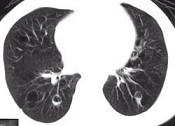

问题 女,23岁,咳嗽咳痰反复发作,根据CT图像,应考虑为 ( )

选项 A.支气管扩张并感染 B.多发肺气囊肿 C.多发性肺囊肿并感染 D.多发性肺脓肿 E.大叶性肺炎

答案 C